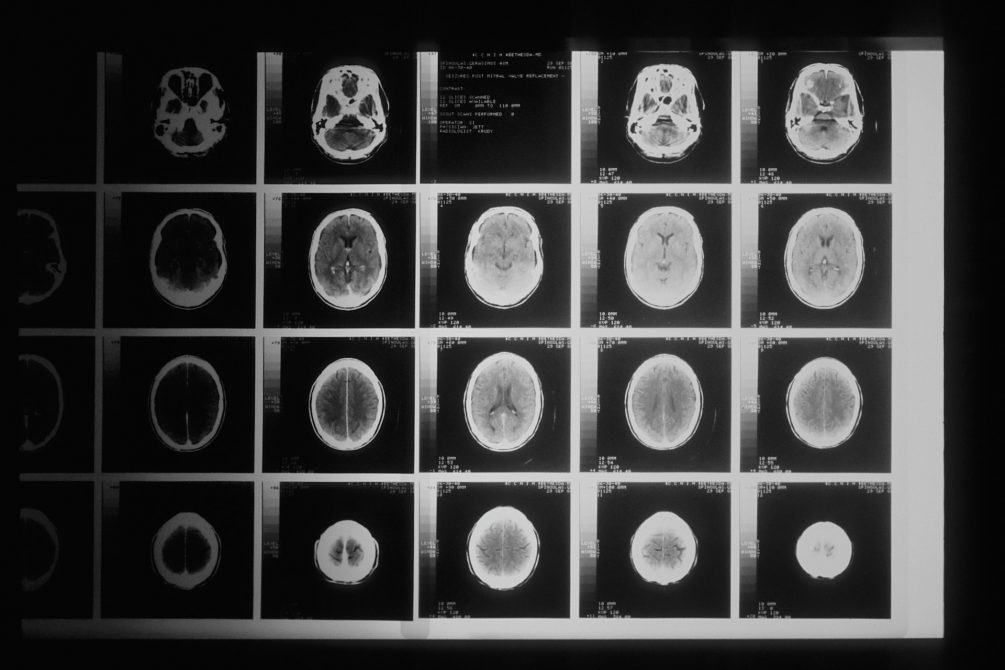

Одно из последних исследований подтвердило необычную активность мозга в момент остановки сердца. В частности, у умирающих пациентов наблюдался всплеск активности гамма-волн, которая считается самой быстрой мозговой активностью. Это уже назвали потенциальными нейросигналами сознания, которые могут свидетельствовать о том, что жизнь после смерти есть, а тело покидает душа.